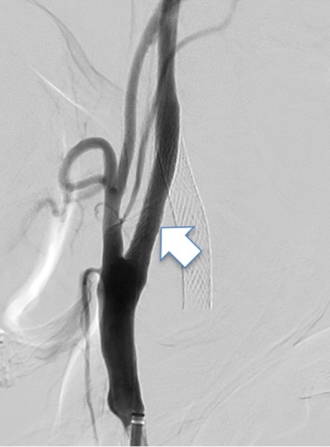

動脈の内部にプラークという脂の塊が貯まることで血管が細くなる病気です。脳梗塞の原因となります。ある程度のものであれば内服薬のみで脳梗塞予防が可能になってきていますが、重度のものでは外科的な治療が必要になります。

血管内治療では、狭窄部位にステントを留置することで狭窄した血管を広げることが可能です(下図)。

治療前

治療後